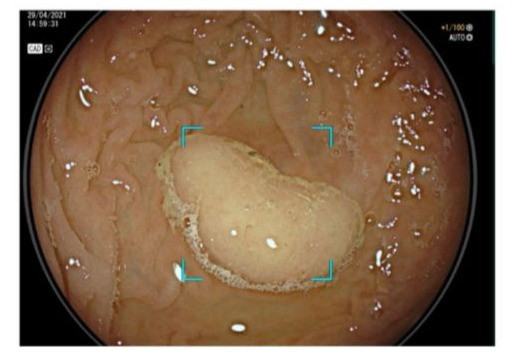

- AI-Assisted Colonoscopy (Endoscopy): One of the most mature applications of AI in gastroenterology is computer-aided detection (CADe) during colonoscopy. Multiple RCTs have evaluated real-time AI systems that automatically flag polyps in the endoscopic video feed. These systems are typically powered by CNNs trained on thousands of endoscopic images of polyps; notable examples include Medtronic’s GI Genius and Fujifilm’s CAD EYE. A 2024 meta-analysis of 44 RCTs confirmed that AI-assisted colonoscopy significantly improves adenoma detection rates (ADR) compared to standard colonoscopy [1]. The pooled ADR increased from ~37% with standard screening to ~45% with AI assistance (relative risk ~1.21) [1]. This translates to a 20-25% relative increase in the detection of adenomatous polyps, which is clinically meaningful given that higher ADR is associated with lower interval cancer rates. Figure 1 illustrates this improvement in ADR. Additionally, the meta-analysis showed that AI reduced adenoma miss rates by over 50% in tandem studies (missed lesions dropping from 35% to 16%). These benefits were consistent across different AI platforms and endoscopist experience levels.

Figure 1: Improved adenoma detection with AI-assisted colonoscopy.

AI-based computer vision acts as a second observer during colonoscopy, identifying polyps that might be missed by the endoscopist. In a meta-analysis of 44 RCTs, integrating AI (CADe) increased the adenoma detection rate from 36.7% to 44.7%, a significant improvement. By catching more adenomas, AI-assisted colonoscopy has the potential to prevent more cases of CRC development.